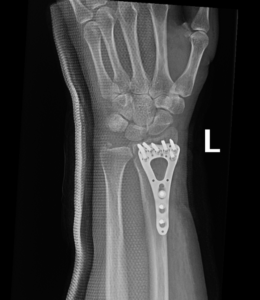

if the fracture is displaced, surgery may be needed to put the bone back into the correct position and fix the bone with Plates & screws or nails for adequate healing to occur.

- Wrist Fractures.